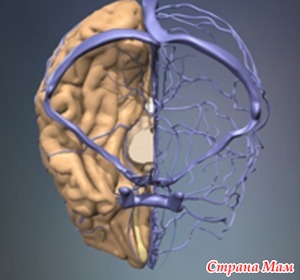

При рождении малыша родители обнаруживают у него на головке особое место – на стыке костей из соединительной ткани образуется особый ромбик, который называют большим родничком. На затылке у ребенка тоже есть малый родничок, а у недоношенных деток – еще и боковые. Зачем же детишкам нужны эти самые роднички? Этот вопрос часто возникает у родителей, им интересно выяснить, какие функции выполняют эти самые роднички и когда они должны в норме закрываться? Читать далее»